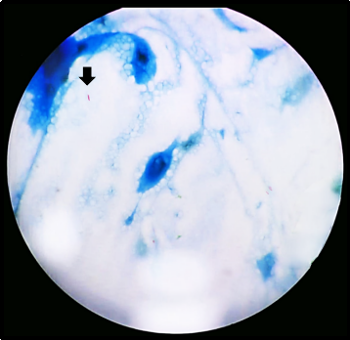

(Fig 3.a, 3.b). On Giemsa stain, deep blue oval

spore like structures were seen (Fig 3.c.).

Modified Acid fast stain (1% H2SO4)

showed acid fast, bright red spores against blue

background (Fig 3.d). On slit lamp examination

| Fig

3c: Giemsa-stained smear showing deep blue

oval spore-like structures suggestive of Microsporidia

(Giemsa stain, ×1000 magnification). |

Fig

3d: Modified Acid fast stained smear

showing acid fast, bright red spores

against blue background (Modified acid

fast, ×1000 magnification) |